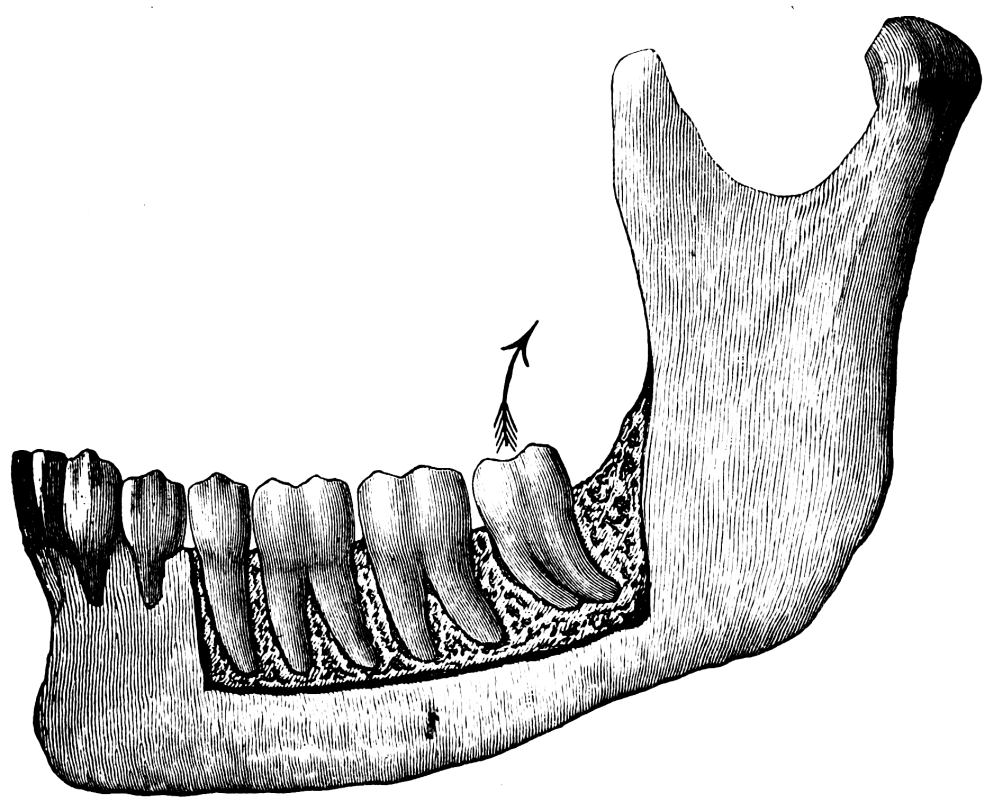

A correct acquaintance with the disposition of the alveoli of the teeth is of importance for skilful and successful operating. Fig. 15 gives a general idea of the appearance of the alveoli, but it is needless to say that a full knowledge can only be really obtained by a careful study of the bones themselves; by this means, too, some idea of the strength of different portions of the alveolar borders can be obtained—a matter of some moment when applying force in the process of removing a tooth from its socket. The points to be specially noted in the maxilla are the thinness of the outer alveolar wall as compared with the inner, the prominence of the canine socket, and the cancellous character of the bone in the region of the third molar. In the mandible the outer alveolar border will be seen to be thinner than the inner, with the exception of that portion in the region of the{13}

Fig. 15.

From the “American System of Dentistry.”

third, and often of the second molar; another fact worthy of attention is that at the posterior portion{14} of the socket of the third molar the bone is moderately dense.